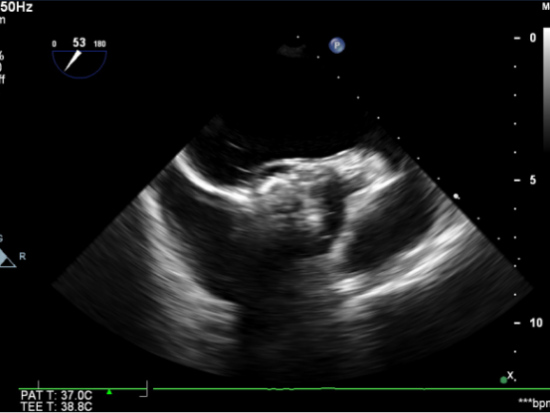

图1. 主动脉瓣钙化明显,并中量反流

图6.TEE提示未见瓣周漏,CW示过瓣流速较术前明显下降